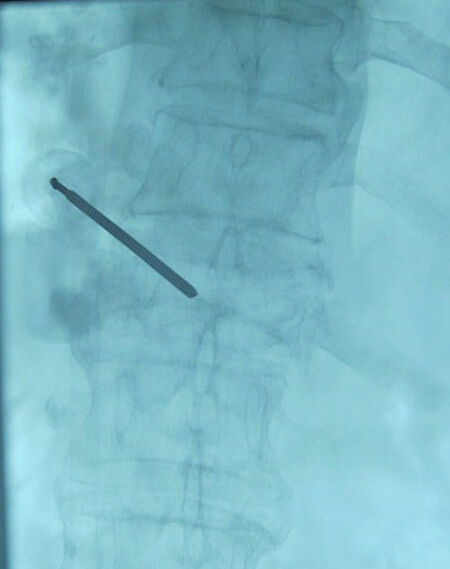

骨水泥注射术(即经皮椎体成形术,PVP)——经皮微创椎体成形术治疗这一顽症。该技术的原理是在大型进口X光机帮助下,将1根细针穿入病变的椎体,然后将骨水泥通过这一细针注入到椎体内部,骨水泥在椎体内凝固后使椎体的稳固性增强,从而达到强化椎体,消除疼痛的效果。手术创伤极小,整个过程在局部麻醉下即可完成治疗,大多数患者在手术结束后即感疼痛症状明显减轻、消失。

女性,81岁,腰背部剧烈疼痛1月,翻身、下床困难,保守治疗及卧床休息无效。无明显外伤史史。术前CT、MRI显示胸12椎体新鲜压缩骨折。行经皮椎体成形术治疗,注入骨水泥。术后疼痛明显缓解,能够轻松地翻身、下床、坐立。

针尖位置满意后,注入骨水泥。图中黑色部分代表骨水泥。骨水泥填在椎体里面,支撑起椎体,将骨折碎片粘在一起,就能明显减轻疼痛。当然要准确判断到底是哪一个椎体出了问题。